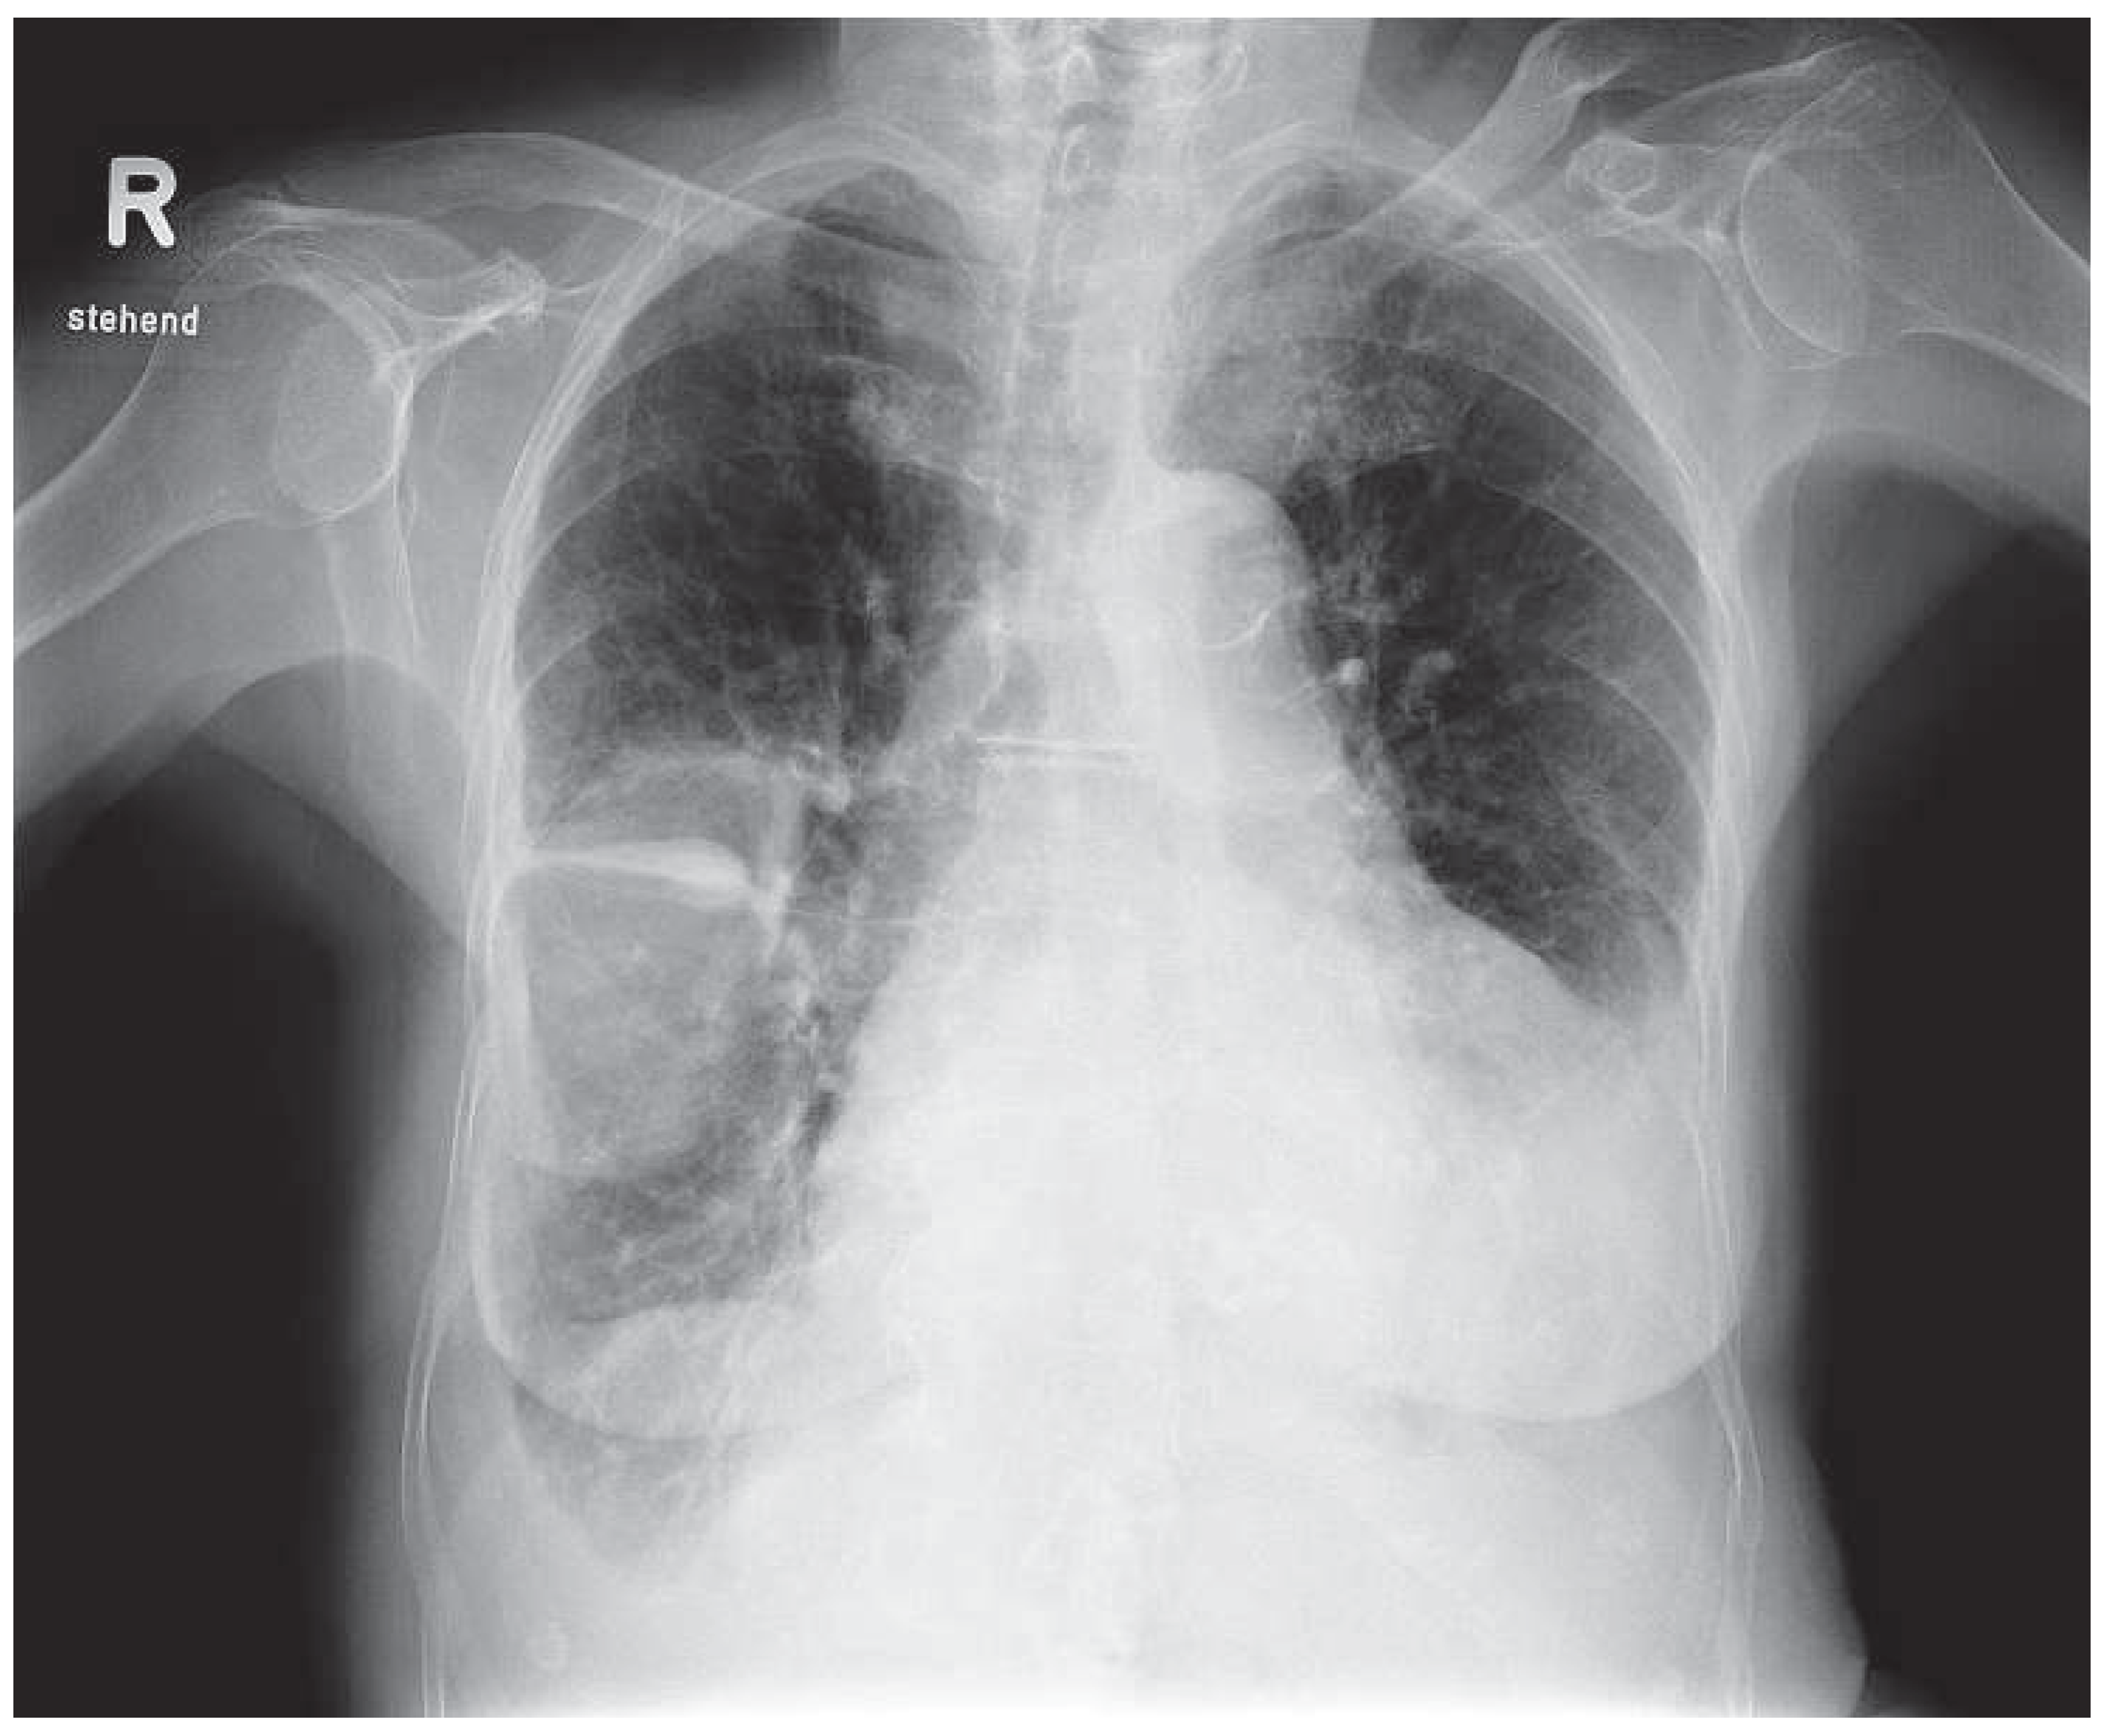

Phantom Tumour of the Lung

Case report